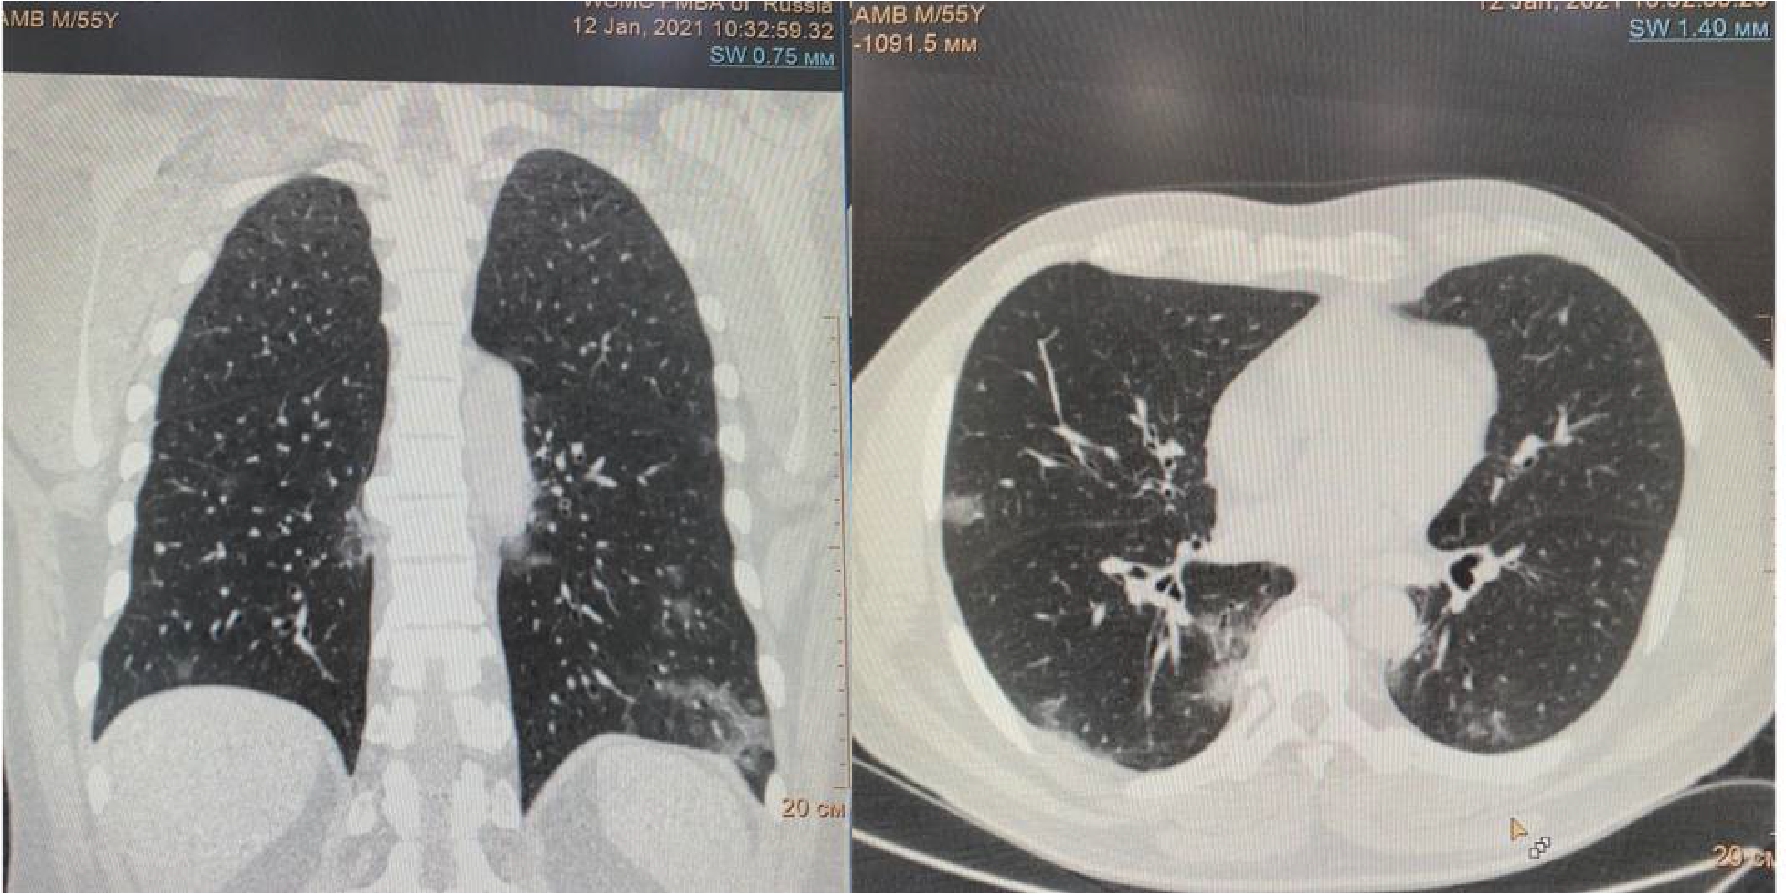

На 16 сутки госпитализации пациент начал жаловаться на резкое усиление одышки даже в покое, невозможность находиться в прон-позиции. МСКТ органов грудной клетки обнаружила уменьшение объема поражения легких до 30%, также был впервые выявлен спонтанный средний правосторонний пневмоторакс (рис. 3).

Рисунок 3. МСКТ органов грудной клетки – признаки двусторонней полисегментарной интерстициальной пневмонии (объем поражения 30%, КТ-2). Средний правосторонний пневмоторакс (красные стрелки).

Появлению данного осложнения не предшествовали какие-либо инвазивные манипуляции в области дыхательных путей, пищевода, пациент не находился ИВЛ. Однако возникновение ПТ коррелирует усугублением дыхательной недостаточности, снижением SpO2 (рис. 4) с пиком ЛДГ (до 397 ед/л), уровень которого прогрессивно возрастал на протяжении всего лечения (рис. 5).